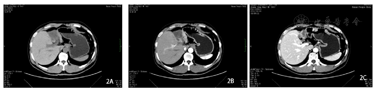

入院后完善相关检查,给予护肝、营养支持等相关对症治疗,经过我院多学科团队(multi-disciplinary team,MDT)会诊认为,虽然患者手术意愿强烈,但肿瘤负荷大,且门静脉主干及左右支都存在癌栓,如进行手术治疗患者不获益的可能性较大,可先给予转化治疗。经充分知情同意后,于2021年10月20日至2022年3月21日行派安普利单抗200 mg免疫治疗(静脉滴注,每3周1次),同时于2021年10月20日至2022年4月4日联合口服盐酸安罗替尼12 mg(服用2周停1周)靶向治疗,其中在2021年10月25日行肝动脉灌注化疗,后患者无法耐受拒绝再次肝动脉灌注化疗治疗。每3个免疫治疗周期复查一次,2021年12月26日CT检查结果提示:肝脏4段段病灶范围较前缩小,密度较前减低,门静脉主干内血栓范围较前缩小,余无特殊。2022年3月21日CT检查结果提示:肝脏4段段病灶范围较前缩小,密度较前减低,左肝外叶新增无强化低密度灶较前缩小,门静脉主干内血栓基本吸收,余无特殊(图2)。甲胎蛋白和异常凝血酶原明显降低(图3)。治疗过程中2022年1月19日出现低钾电解质紊乱,予以补钾维持水电解质平衡。2022年3月21日复查达到部分缓解,但出现甲状腺功能减低,经院内MDT讨论本周期后停药派安普利单抗,口服甲状腺素片,定期复查甲状腺功能,待正常择期行左半肝切除术。2022年5月4日MRI检查结果提示:原S4占位较前明显缩小,较大横面约72 mm×43 mm,门静脉内癌栓较前明显减少,2022年5月4日甲状腺功能正常后,完善术前准备,评估肝功能为Child-pugh分级A级,吲哚菁绿排泄实验:6.8%,测量残肝体积为:60.5%。于2022年5月10日行左半肝切除+胆囊切除胆道探查+胆肠内引流+门静脉节段切除重建+膈肌部分切除术。术后病理学检查结果示:(1)送检肝肿块切除标本,多个肿物内大部分为凝固性坏死,仅残留一小灶癌(镜下最大径3 mm),为肝细胞癌Ⅲ级,并可见异物巨细胞反应及蓝染无结构物,符合肝动脉化疗栓塞术后改变。肿物紧邻被膜下,未累及膈肌,肝切缘净。(2)慢性胆囊炎,胆囊结石,胆囊颈部淋巴结反应性增生。(3)12组淋巴结镜下可见纤维脂肪组织,伴炎细胞浸润,未见癌。(4)门静脉壁未见癌,癌栓已完全坏死。(5)胆管壁慢性胆管炎,纤维组织增生。免疫组化(图4):CA19-9(-)、CD34(血管+)、CK7(-)、CK8/18(+)、Glypica n﹣3(+)、Arg-1(+)、Hepatocyte(+)、CEA(-)、Ki67(+,25%)、p53(-)、Syn(-)、GS-6(+)。